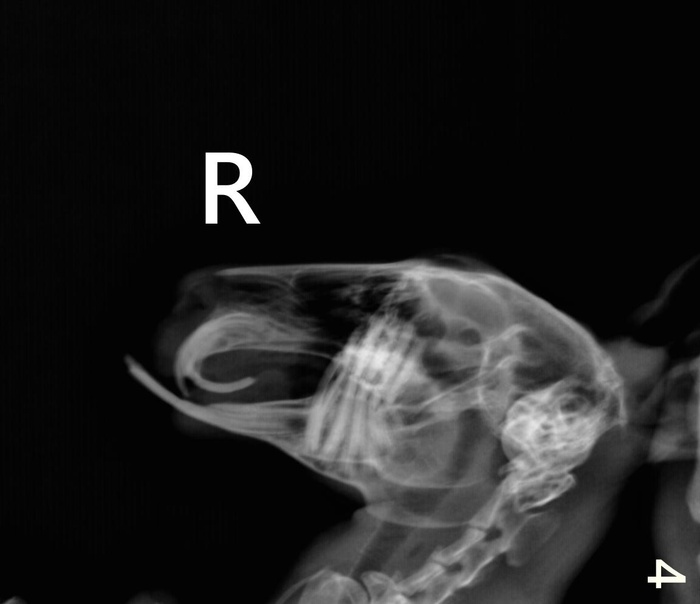

На видео ниже Анфиса с удовольствием лопает специальный корм который выглядит как прессованное сено. Сено ей настоятельно рекомендовано ветврачами ветклиники после укорачивания зубчиков, чтобы вновь не переросли. Ест и слышно как хрустит премалывая словно жерновами гранулы корма. Надеемся что это именно то что нужно и корм поможет стачивать задние зубки у Анфисы, ибо просто сено, даже разных марок, она кушать не хочет. Кормим, и не только им,  ждем результата. Что с зубами можно увидеть на рентгене.